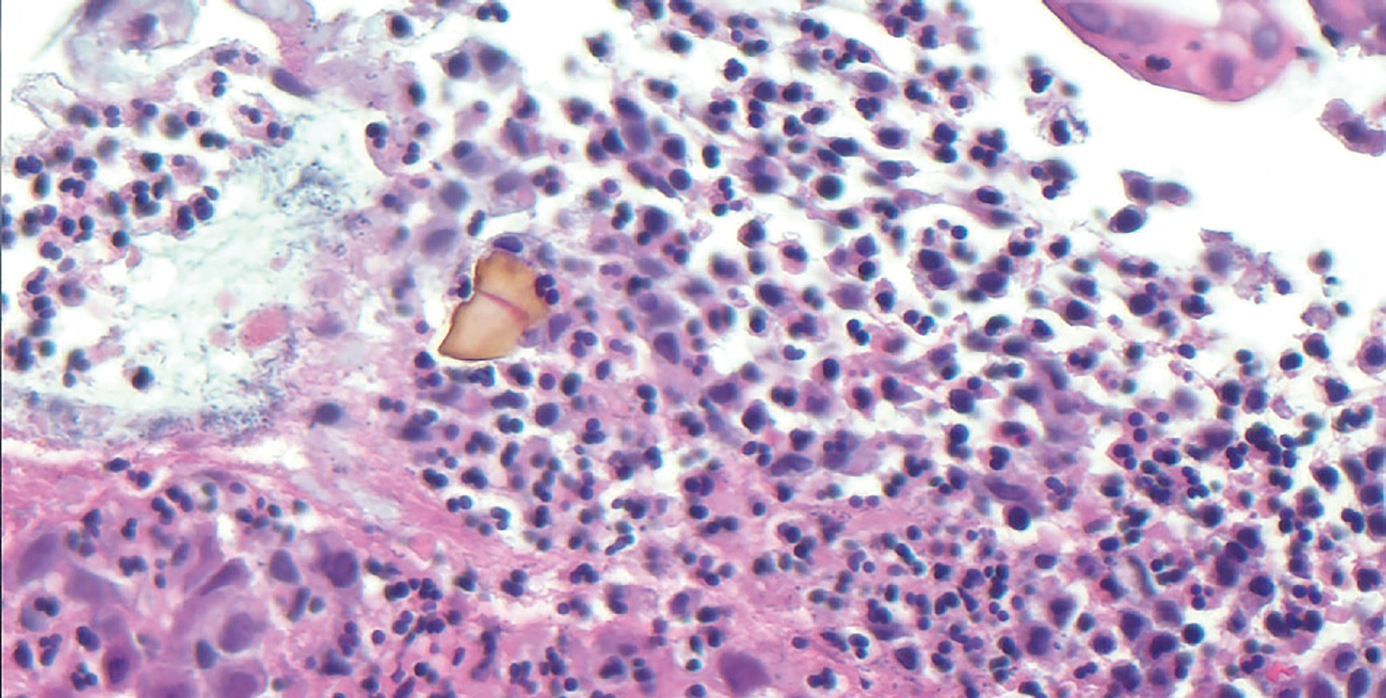

Kolitis durch Sevelamerkristalle

Sevelamer ist ein weit verbreitetes, nicht auf Kalzium basierendes, phosphatbindendes Mittel, das zur Senkung des Serumphosphatspiegels bei chronischer Nierenerkrankung (CKD) und Nierenerkrankung im Endstadium (end-stage renal disease, ESRD) eingesetzt wird. In der Regel ist es gut verträglich, in einzelnen Fällen kann es jedoch zu Verletzungen der Magen-Darm-Schleimhäute als Folge der Einnahme kommen.

• Hämatoxylin-Eosin-Färbung

• Kolitis

• Magen-Darm-Schleimhaut

• Mukosa

• Sevelamer

• Sevelamerkristalle